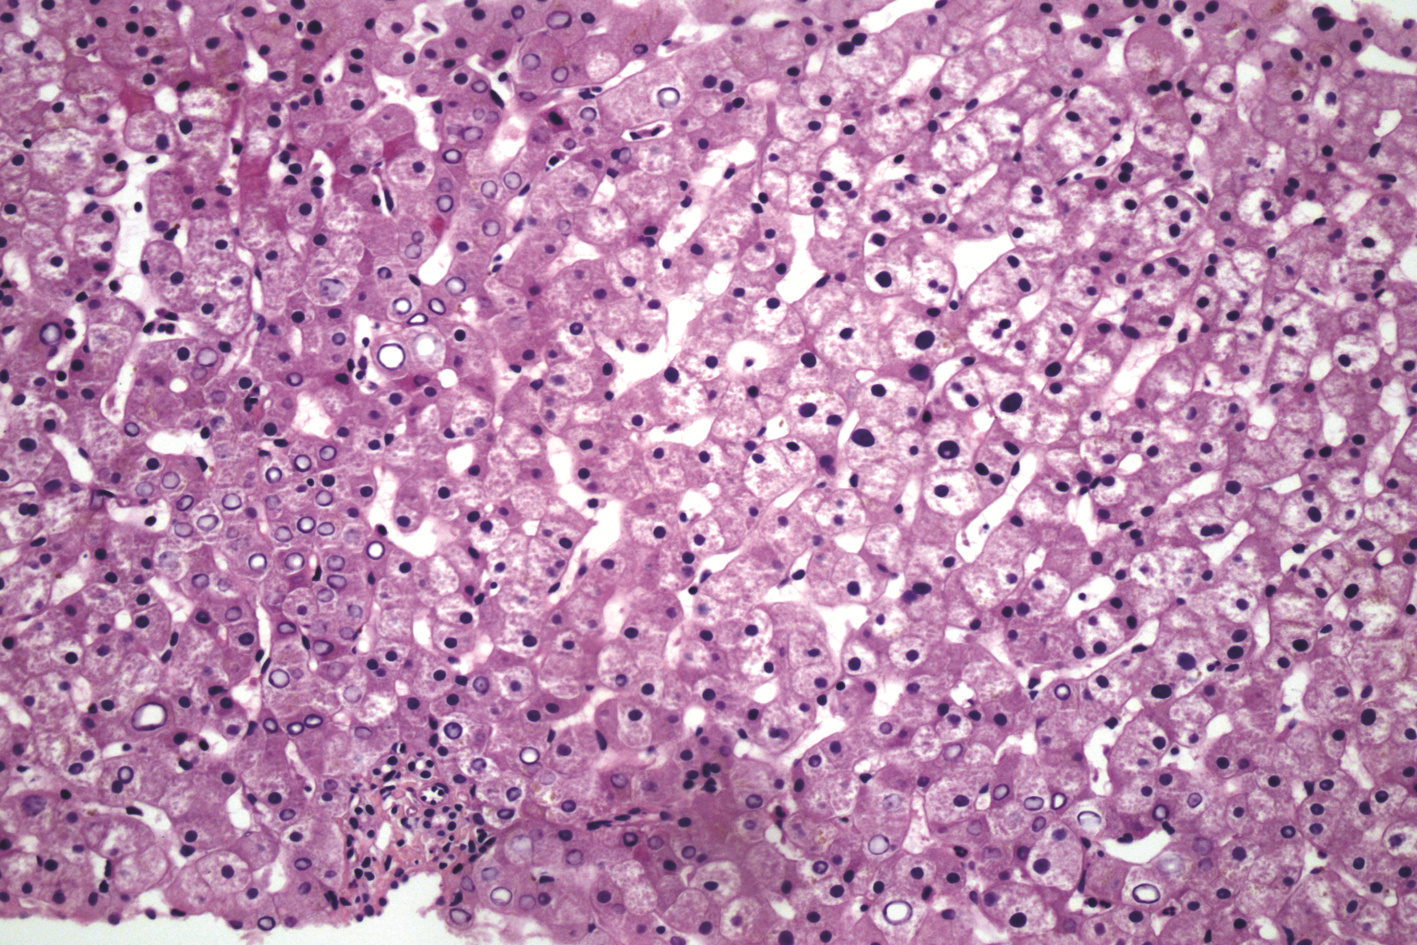

A case of eosinophilia mainly manifesting as liver injury

Hao WU, Xin ZHENG, Lei ZHU, Dong YANG

2022, 38(4): 883-885. DOI: 10.3969/j.issn.1001-5256.2022.04.027

Abstract(2133) HTML (304) PDF (2636KB)(146)

Abstract: